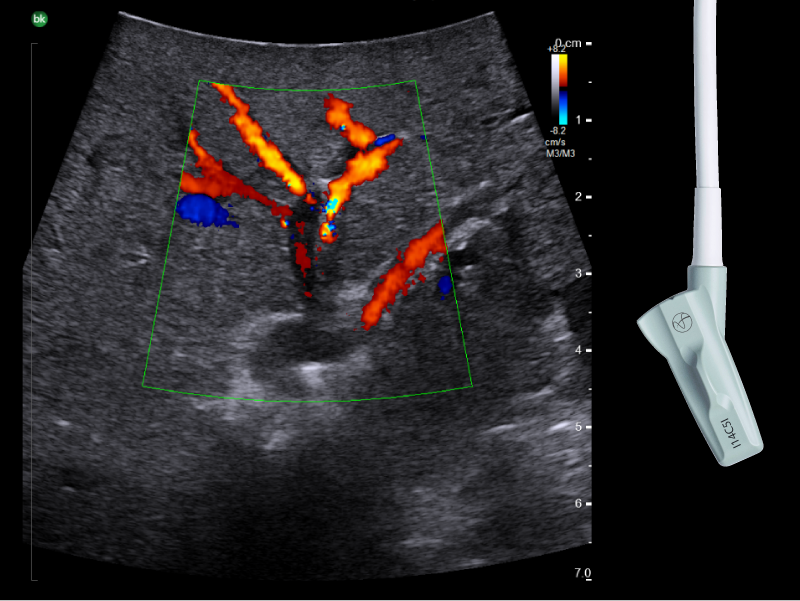

Liver mass, visualized with I-Shaped Transducer